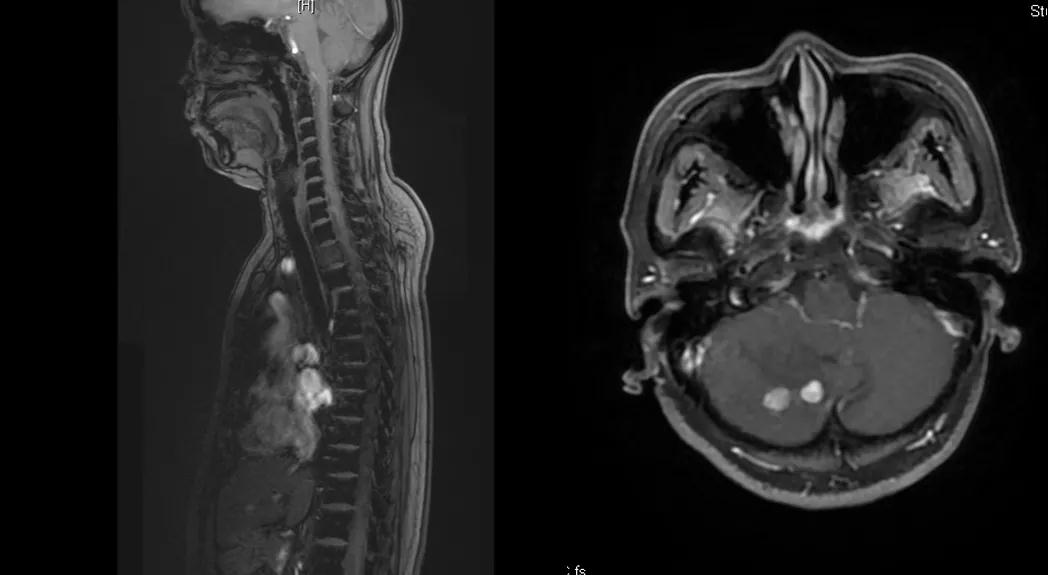

曲妥珠单抗辅助治疗结束6个月后,患者出现左侧胸部疼痛,ECT检查提示:左侧第4、5肋骨及T2胸椎转移;MR提示:T2椎体转移,肝S6段异常强化灶,考虑转移瘤可能性大;脑转移(图1)。

图1

给予T-DM1治疗。治疗6个月后复查MR显示脑、肝、骨转移瘤均较前明显缩小,达到部分缓解(PR)(图2)。目前PFS已达10+个月。

图2

患者为ⅢA期(cT3N1M0)、三阳性乳腺癌,经AC-TH新辅助治疗达到降期(ypT2N0M0)。患者内分泌+抗HER2辅助治疗结束6个月时出现转移进展(脑、肝、骨),给予THP一线治疗,因无法耐受毒副作用而改为T-DM1,治疗6个月达到肝、脑、骨转移PR,患者目前中位PFS已超过10个月,T-DM1治疗过程中仅出现轻度CIT,且可自行恢复。